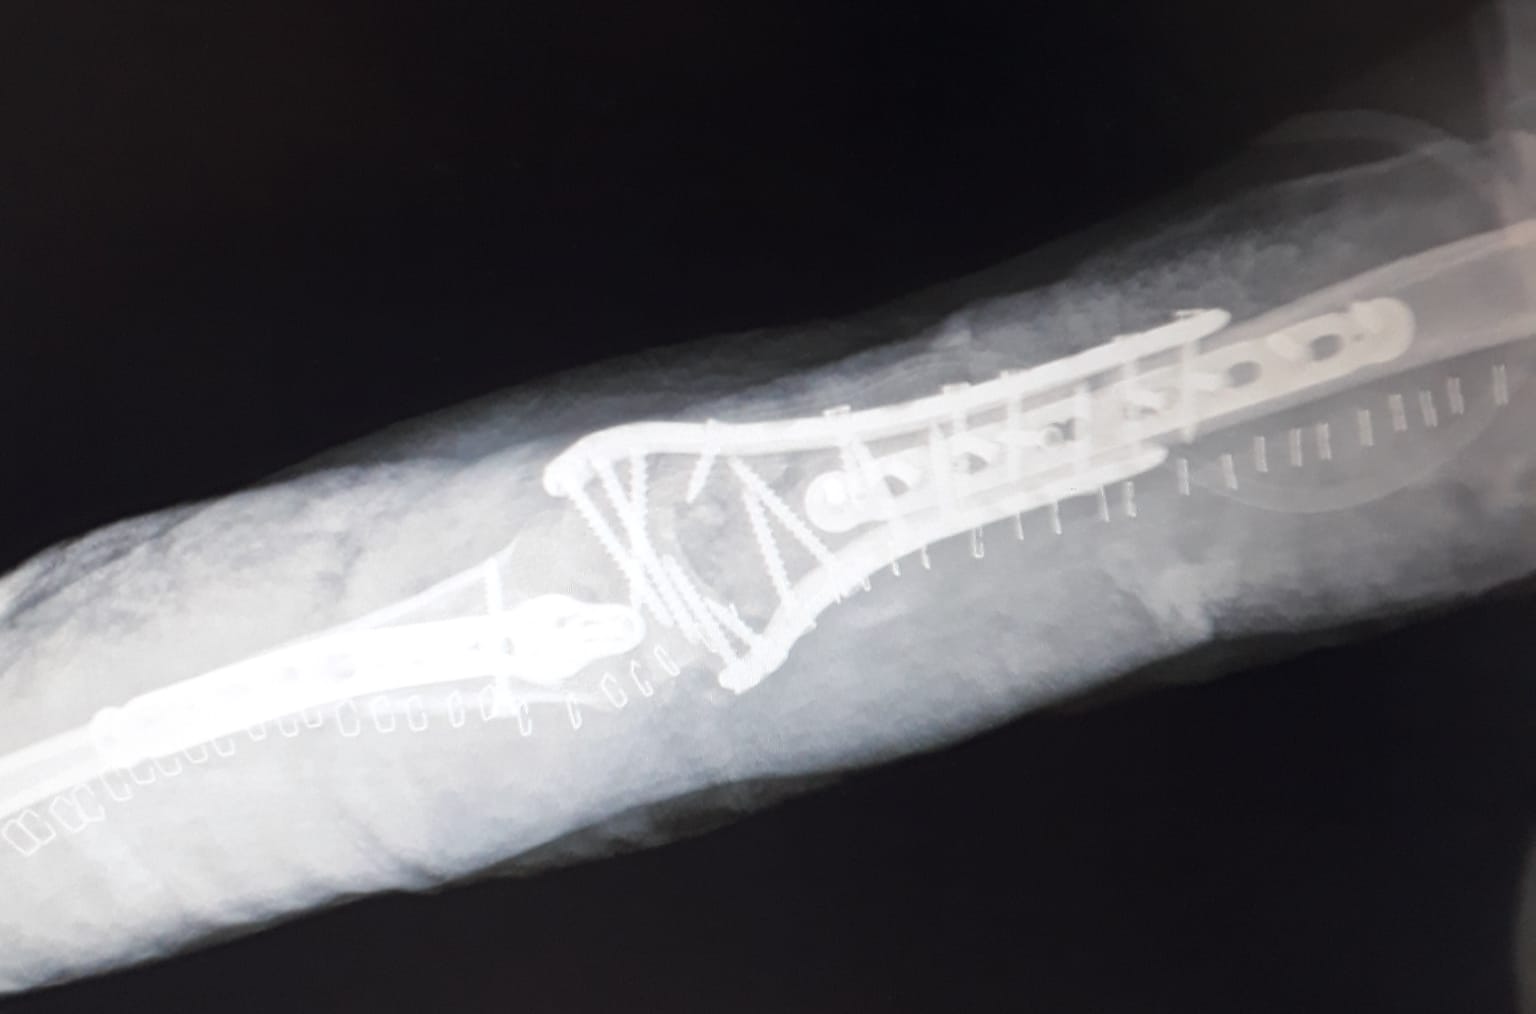

Images Gallery